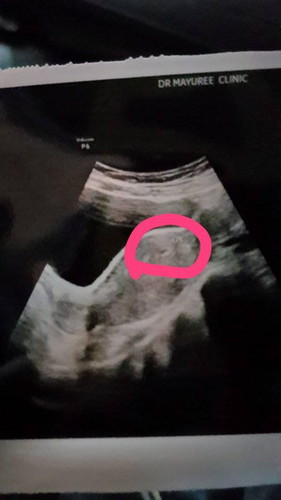

ตั้งครรภ์ได้ 5 สัปดาห์แล้วค่ะ แต่ถ่ายไปแค่ครั้งเดียว ทานน้ำ ทานผลไม้และน้ำผลไม้ ก็ไม่ถ่ายค่ะ ปวดท้อง มีลม แต่ถ่ายไม่ออก ทำอย่างไรดีคะ